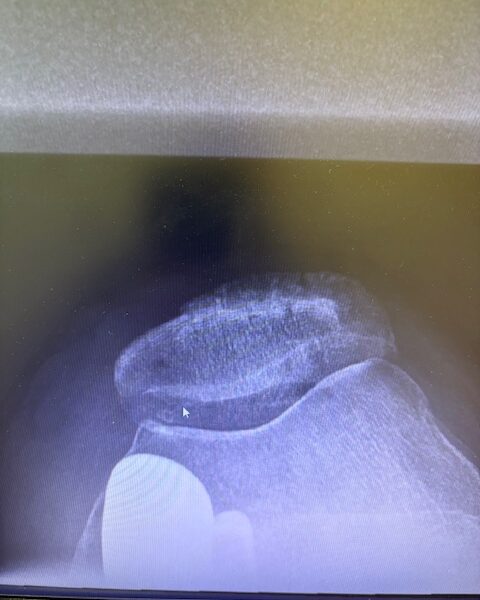

Ο ακτινολογικός έλεγχος (ακτινογραφίες/μαγνητική τομογραφία) ανέδειξε προχωρημένη οστεοαρθρίτιδα του έσω κονδύλου, με πλήρη διατήρηση του έξω διαμερίσματος και της επιγονατιδομηριαίας άρθρωσης. Με βάση αυτά τα ευρήματα, ο ασθενής ήταν ιδανικός υποψήφιος για μερική (μονοκονδυλική) αρθροπλαστική γόνατος.

Πραγματοποιήθηκε απεικόνιση και ψηφιακός σχεδιασμός της επέμβασης, ώστε να προσδιοριστεί με ακρίβεια το μέγεθος και η θέση των προθέσεων. Ο στόχος ήταν να αποκατασταθεί η φυσιολογική μηχανική του γόνατος, διατηρώντας ανέπαφα τα υγιή τμήματα της άρθρωσης, τους συνδέσμους και τους γύρω μυς.